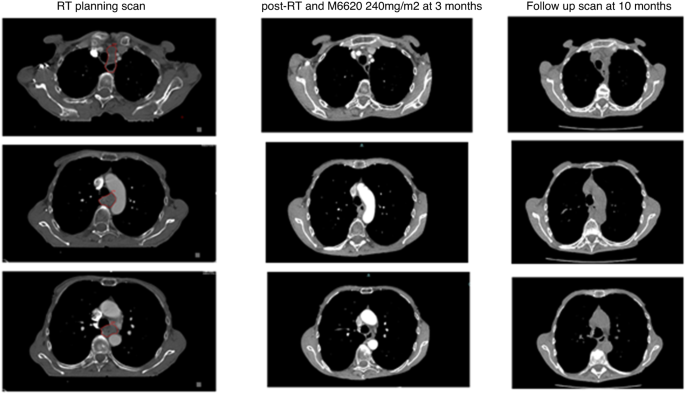

Figure 3 shows the excellent radiographic response of a patient in cohort A1 with a mid-oesophageal SCC at 25 cm T4N2M1 3 months following treatment with RT + berzosertib. A further scan 6-months later shows no reported change in the oesophageal tumour and no size-significant mediastinal adenopathy.